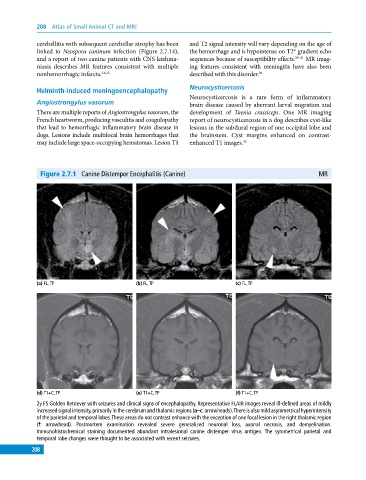

Figure 2.7.1 Canine Distemper Encephalitis (Canine) MR

(a) FL, TP (b) FL, TP (c) FL, TP

(d) T1+C, TP (e) T1+C, TP (f) T1+C, TP

2y FS Golden Retriever with seizures and clinical signs of encephalopathy. Representative FLAIR images reveal ill‐defined areas of mildly

increased signal intensity, primarily in the cerebrum and thalamic regions (a–c: arrowheads). There is also mild asymmetrical hyperintensity

of the parietal and temporal lobes. These areas do not contrast enhance with the exception of one focal lesion in the right thalamic region

(f: arrowhead). Postmortem examination revealed severe generalized neuronal loss, axonal necrosis, and demyelination.

Immunohistochemical staining documented abundant intralesional canine distemper virus antigen. The symmetrical parietal and

temporal lobe changes were thought to be associated with recent seizures.